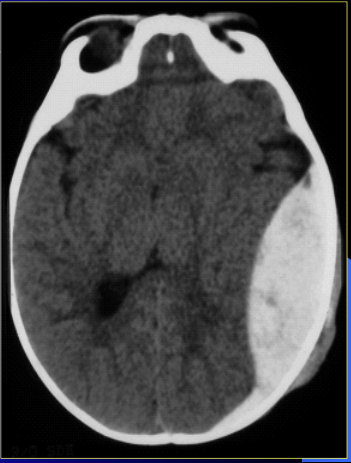

is this T1, T2, CT?

what is the pathology?

CT

epidural hematoma

is this CT or MRI?

hemorrhage

if someone has a hemmorrhage, what imaging is the best?